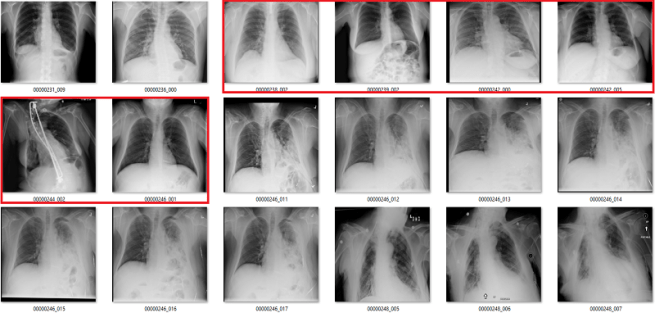

Complete nonsense as far as I can tell. Below are the model predictions, compared against the labels in the dataset. Again, the same technique as earlier for picking images. I’m confident these aren’t cherry picked.

True positives

The green ones are the only actual true positives. The rest have incorrect labels.

True negatives

There are one or two arguable ones in the top 18, but I gave the labels the benefit of the doubt. The red ones in the 2nd 18 are all wrong.

False positives

The red ones are wrong. It also turns out that there are rotated, inverted, distorted, and otherwise abnormal images in the dataset (shown by the red question mark). More on that in the next post.

False negatives

Again, the red ones are wrongly labelled.

Despite an apparent AUC of 0.7 we get really bad classification performance, in line with the label inaccuracy. The model didn’t just ignore the incorrect labels and produce sensible predictions. It was not robust to label noise. Most importantly, the AUC value does not reflect the clinical performance.

This is a huge problem.

This AI system learned to reliably produce meaningless predictions. It managed to learn image features that create the above groups of “opacity” cases with almost no airspace opacities, and “no opacity” cases with big groups of severely abnormal lungs.